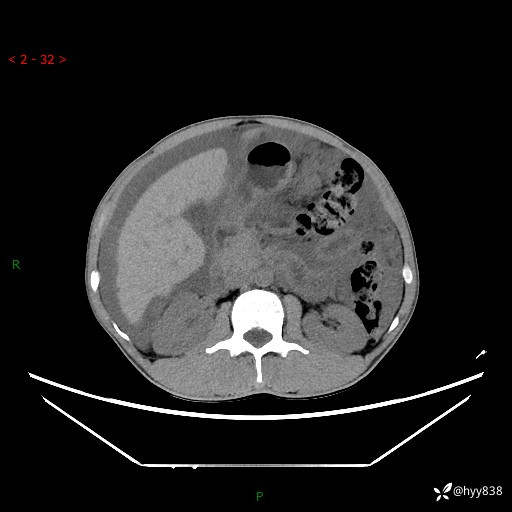

现病史:患者10天前无明显诱因出现腹部胀痛不适,无畏寒发热,无胸痛胸闷,无心慌气短,无恶心呕吐,无腹泻及黑便,无粘液血便及里急后重等症状,4天前在当地县人民医院就诊,行腹部CT示:下腹部占位性病变,腹腔及盆腔积液;今患者为求进一步诊治来我院治疗,门诊以“腹水”收治入院。 发病以来,精神饮食可,大小便正常,体重体力无明显变化。

腹部CT平扫+增强